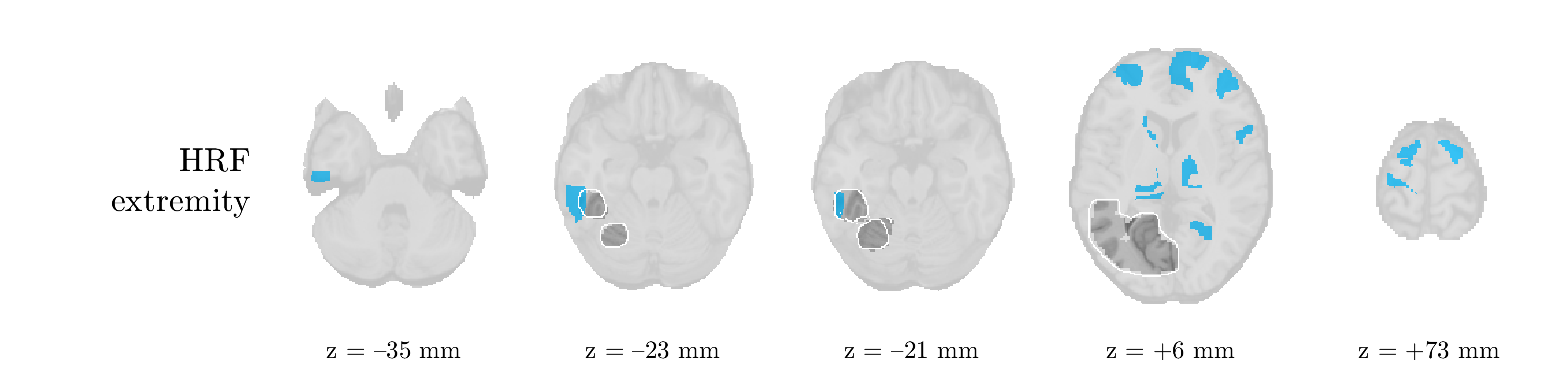

Patient 9

We analyze the solution with sources, and show the results in Figure 15 and 16. In this patient, there is only a moderate correlation of a component with the MWF reference time course. This component’s topography (left occipital) agrees with the clinical description, however. The HRF extremity (and not the entropy) is high in a small part of the IOZ. Both the significant IED activation and deactivation allow correct localization as well. The second source seemingly captured high-frequency oscillatory activity in the sensorimotor network, similar to the previous patient.